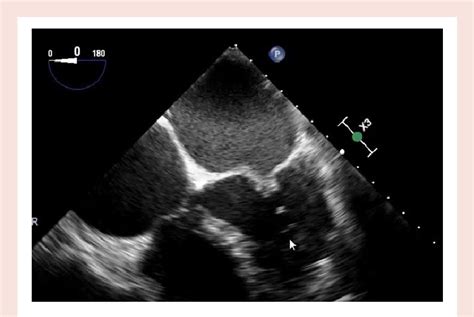

The hockey stick appearance in echocardiography refers to a characteristic shape or trajectory of a structure within the heart, most commonly seen when evaluating the mitral valve apparatus. Imagine a normal mitral valve leaflets opening and closing gracefully. Now, picture one of those leaflets, or a part of it, moving in a way that creates a sharp, angled curve, resembling the blade of a hockey stick. This isn’t a normal finding, and it usually points to something specific going on with the heart’s anatomy or function. It’s a visual clue that helps doctors understand how blood is flowing and how the heart valves are working. The key here is the abnormal movement and shape. It’s often associated with conditions that affect the mitral valve’s ability to close properly, leading to blood leaking backward (mitral regurgitation). This visual can be seen in various views during an echocardiogram, but specific angles are more likely to highlight this characteristic shape. The diagnostic power of this sign lies in its ability to suggest certain underlying pathologies without needing more invasive tests immediately. It’s a testament to how advanced ultrasound technology can visualize intricate details of the heart in real-time. We’ll get into the specific conditions it signals next, but for now, just remember it’s a visual cue of abnormal movement, often at the mitral valve, looking like a bent stick.

Let’s talk more about the main event when it comes to the hockey stick appearance : Mitral Valve Prolapse, or MVP. This is where the connection is strongest, guys, and understanding this relationship is key. MVP is a pretty common condition where the heart’s mitral valve doesn’t close quite right. Normally, the two leaflets of the mitral valve snap shut tightly when the left ventricle contracts, preventing blood from flowing backward into the left atrium. But in MVP, one or both of these leaflets are a bit floppy and can bulge, or prolapse , backward into the left atrium during contraction. The hockey stick appearance on an echo is essentially a visual representation of this prolapse. Imagine the leaflet as a flag. When it prolapses, it doesn’t just flop; it can curve and bend in a way that distinctly resembles the blade of a hockey stick, particularly when viewed from specific angles during the echocardiogram. This visual is particularly evident when the prolapse is significant and causes the leaflet to extend unusually far back. It’s not just about the shape, though. The echocardiogram will also show what this prolapse is doing. Is it causing the valve to leak? This is called mitral regurgitation. The severity of the regurgitation can range from trivial to severe, and it’s a crucial part of assessing the impact of MVP. The hockey stick appearance often goes hand-in-hand with evidence of mitral regurgitation on the echo, like a backward jet of blood seen on Doppler imaging. For patients with MVP, the hockey stick sign is a clear indicator to the cardiologist that the prolapse is present and potentially significant. It helps them classify the severity of the MVP and decide on the best course of management. While not everyone with MVP will show a classic hockey stick appearance, its presence is a strong corroborating finding for the diagnosis and can help in understanding the mechanism of any associated mitral regurgitation.